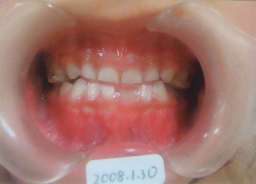

| 歯は自然に生えてくるのでそのまま予後観察 上記の約2年6カ月後 綾、中学1年生、後戻りもなく予後良好 矯正終了 |

上顎の歯 歯磨きはあんまりしないので、軽度の歯周炎が ありますが、 フッ素塗布とフッ素飲料とシーラントでむし歯ゼロです。 2015年04月現在 |

| 幼稚園の時から始めた矯正が、永久歯が 全部生えそろって中学生になりました。 右が長女の綾、左が次女の舞 |

| 2017年04月、高校一年生と中学2年生になりましたが、予後良好でむし歯も一本もありません。 歯も1本も削っていません。 この写真を撮るまで9年かかりました。 タイトル 「小学→中学→高校→そして未来に」 |